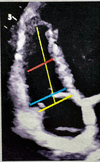

34

What does this image show? what window?

RV linear dimensions: basal (blue) mid (red) longitudinal (yellow) A4C RV focused